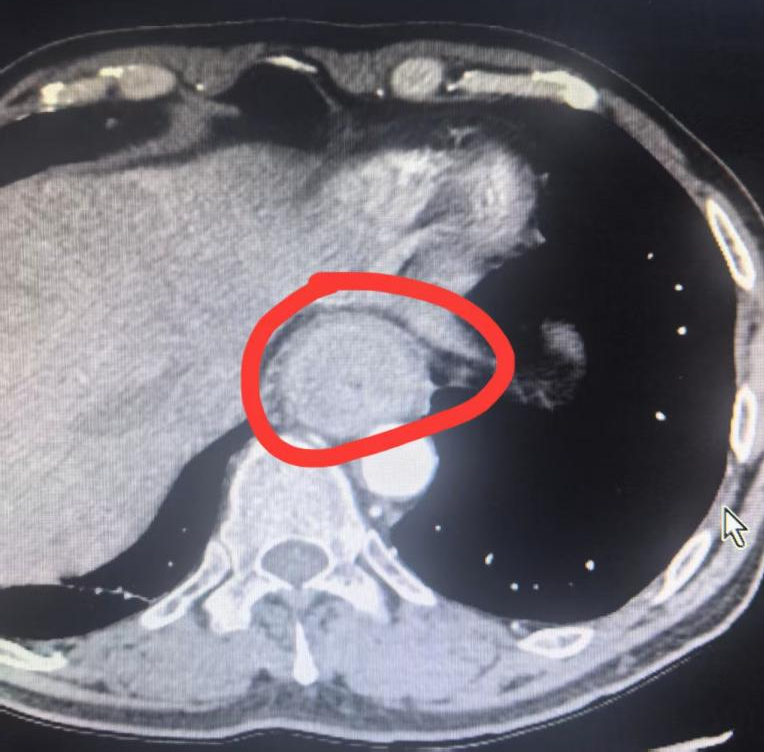

66 岁的王大爷(化名)半年前感觉吃东西有些不顺畅,喉咙里像是有东西堵着,还有轻微的疼痛。刚开始没太在意,可这种梗阻感愈发严重,在当地医院做了胃镜检查。结果发现,距门齿 22—37 cm 处可见食管不规则隆起,几乎把食管堵住了一半,此前的梗阻感就是因此而来。经过进一步的病理检查,王大爷被确诊为食管鳞状细胞癌。经亲戚介绍,王大爷来到了二附院找到吴云飞博士。

秦大叔(化名),今年 63 岁,于半年前出现进食哽咽症状,初期未予重视,后症状逐渐加重,进食米粉等食物时感到明显吞咽困难。随后,他在家人陪伴下前往当地医院就诊,经系统检查胃镜示食管距门齿约 32-38 cm 环周见不规则隆起性肿物,粘膜质脆,触之易出血,仅能流质饮食。病理结果回示:食管鳞癌。由当地医院转到二附院治疗。